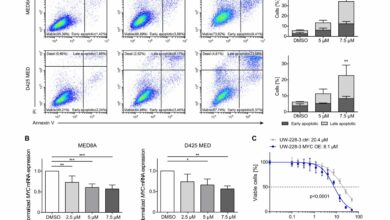

Nova combinação de drogas pode efetivamente tratar tumor cerebral infantil frequentemente fatal

O CI-994 induz a apoptose e diminui a expressão de MYC em linhas celulares de meduloblastoma dirigidas por MYC. (A)…